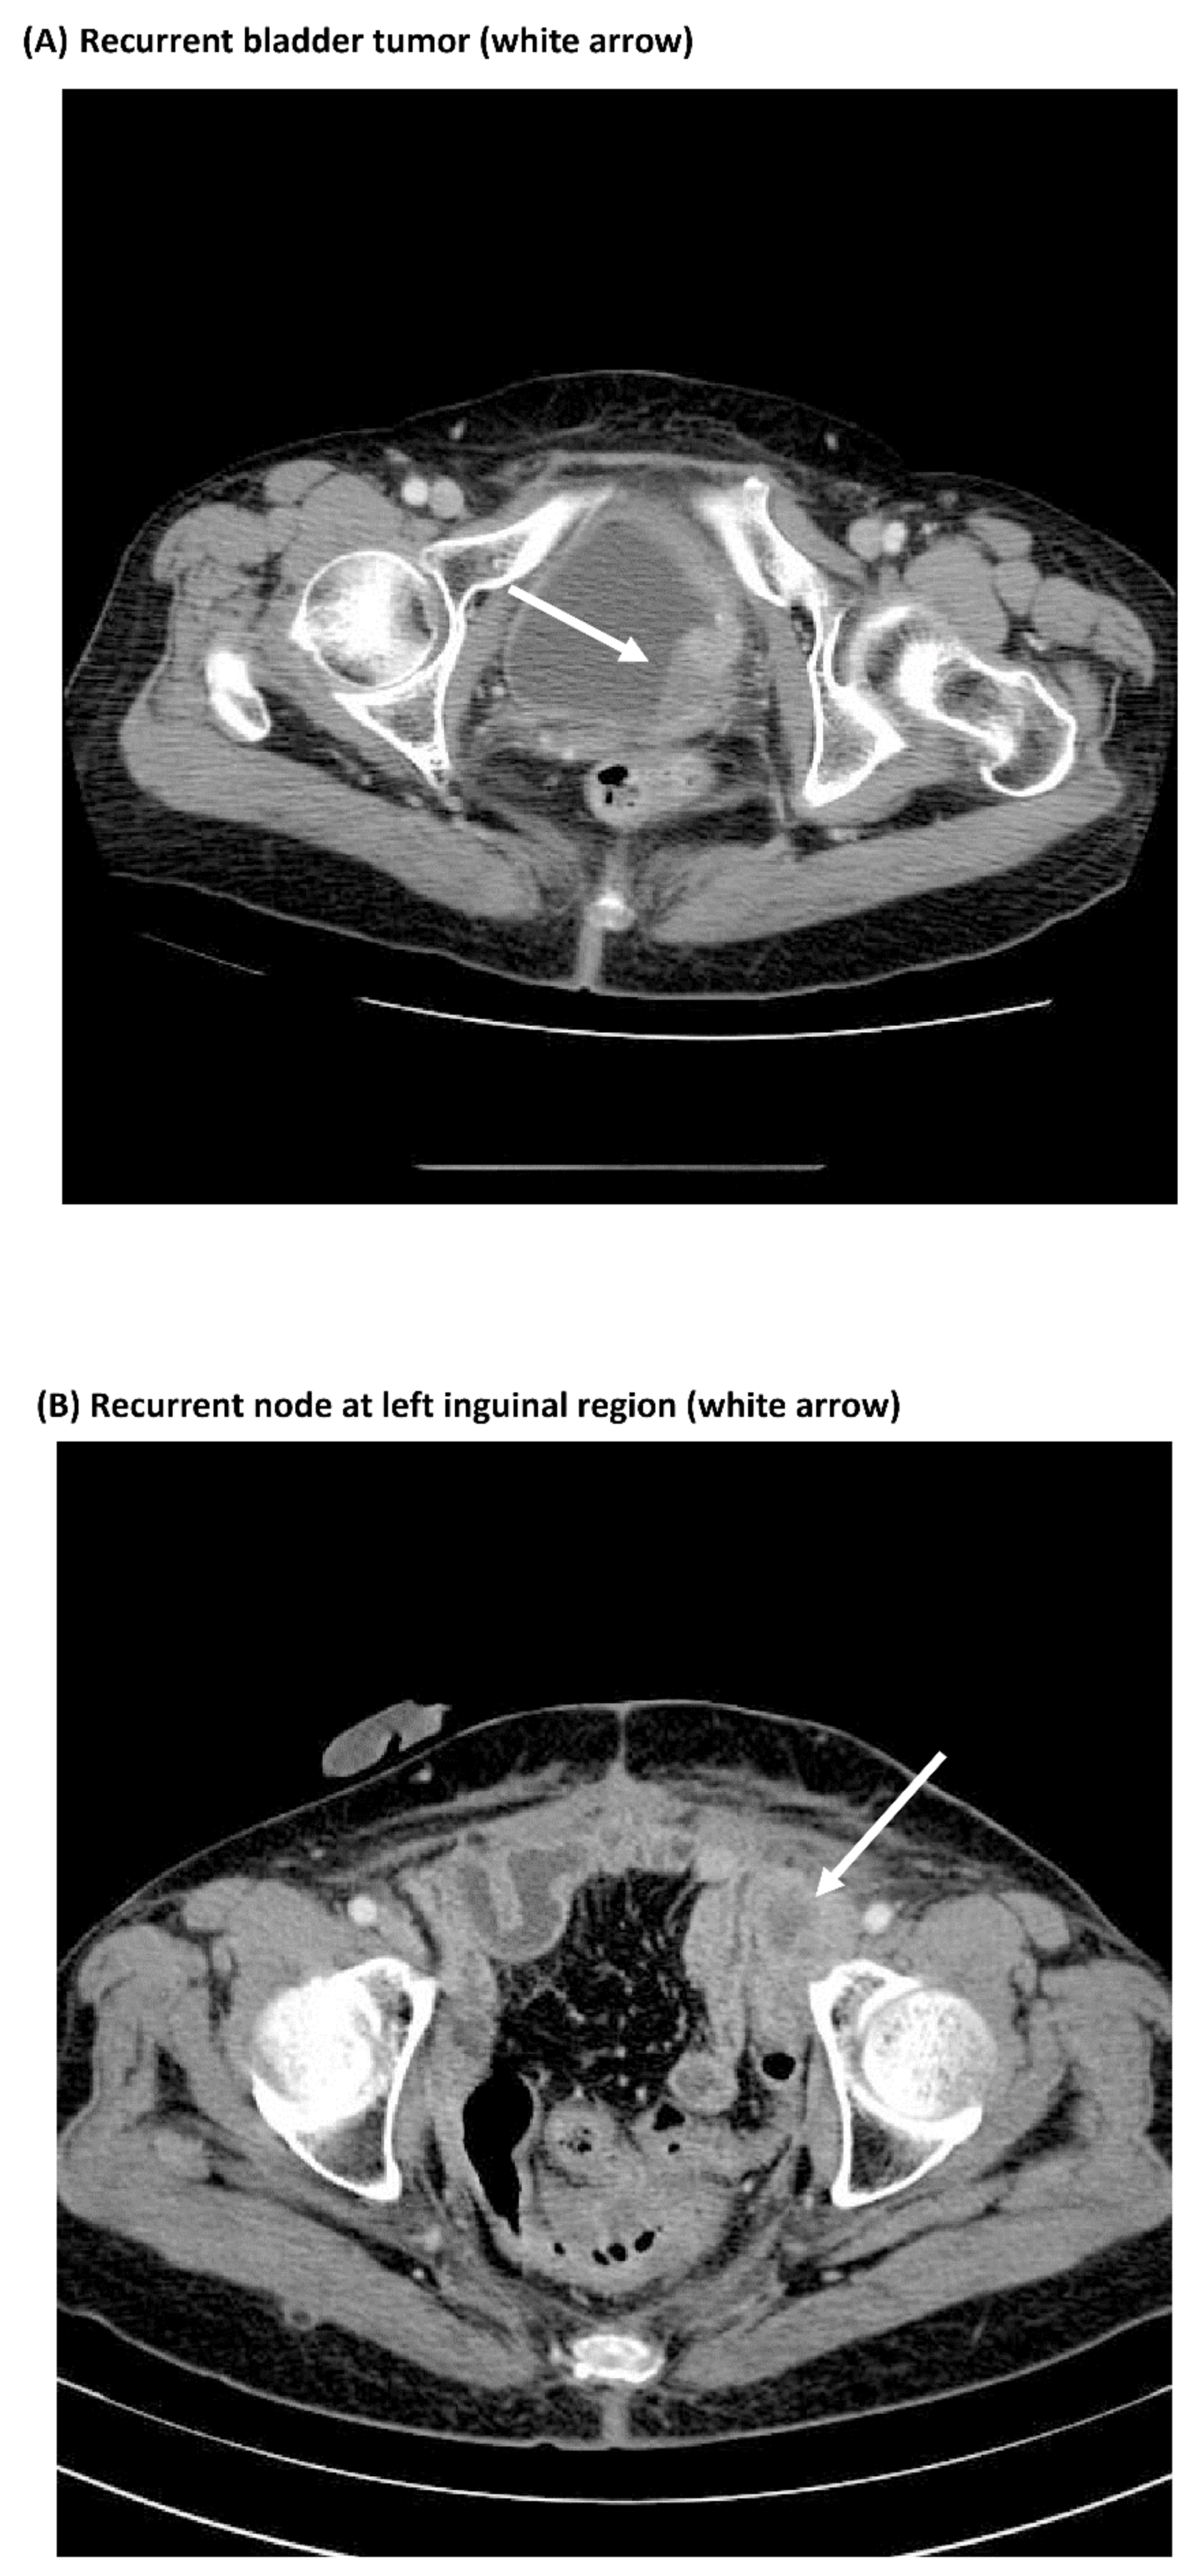

3.3. Comparisons of Immunostaining of NFκB between Pre-Treatment Samples and Recurrent Samples